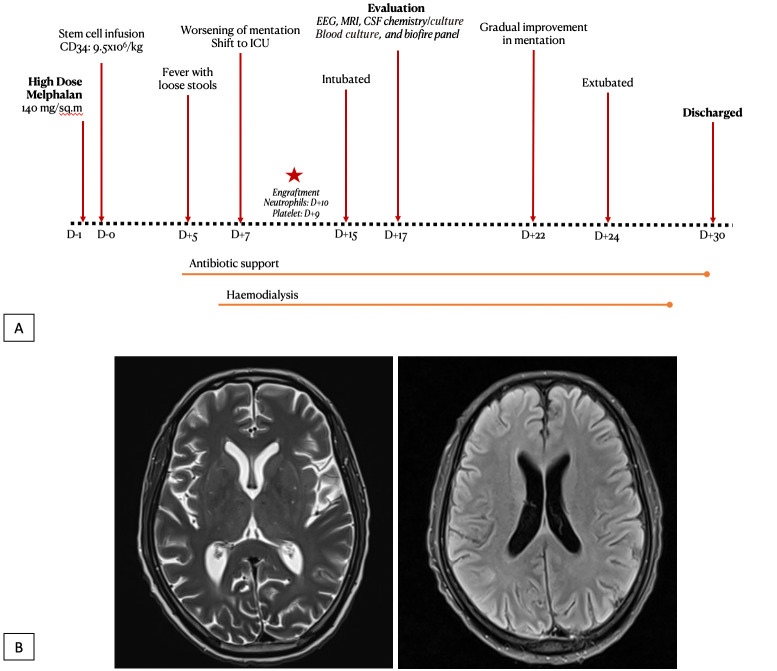

美法仑诱发脑病是接受自体干细胞移植(ASCT)的患者中观察到的一种罕见并发症,其特点是症状从嗜睡到癫痫发作不等。以前的报告曾描述过类似病例,包括对一个大型患者队列的回顾,在该队列中,有2%的接受ASCT的患者发现了美法仑相关脑病。我们描述了一例 63 岁男性多发性骨髓瘤患者的病例,该患者患有基础慢性肾脏疾病(CKD),在接受诱导治疗后完全缓解,但随后出现神经系统恶化,因此需要对多种神经系统和感染病因进行广泛评估。在本报告中,我们强调美法仑相关脑病是骨髓瘤患者(尤其是已有肾功能不全的患者)进行 ASCT 时并发的一种独特病症,并考虑了其处理方法。

Melphalan-induced encephalopathy is a rare complication observed in patients undergoing autologous stem cell transplantation (ASCT) and is characterized by symptoms ranging from drowsiness to seizures. Previous reports have described similar cases, including a review of a large cohort of patients in whom melphalan-associated encephalopathy was identified in 2% of the patients undergoing ASCT. We describe the case of a 63-year-old male with Multiple Myeloma and underlying chronic kidney disease (CKD) who underwent ASCT with a reduced dose of melphalan due to renal dysfunction in complete remission following induction therapy and subsequent neurological deterioration, which necessitated an extensive evaluation of several neurological and infective etiologies. In this report, we highlight that melphalan-associated encephalopathy is a distinct entity complicating ASCT in patients with myeloma, especially in those with preexisting renal insufficiency, and consider its management.